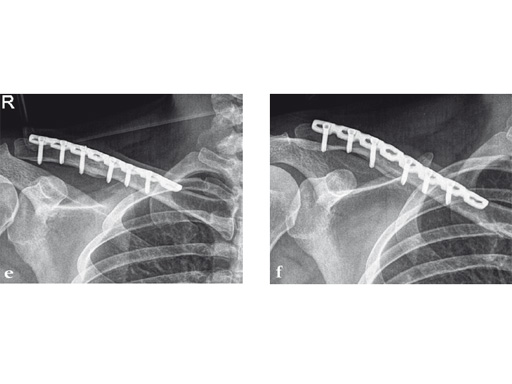

Case 2: a 29-year-old man sustained a midshaft clavicle fracture while playing soccer.

Case provided by Norbert Sdkamp and Martin Jaeger, Freiburg, Germany